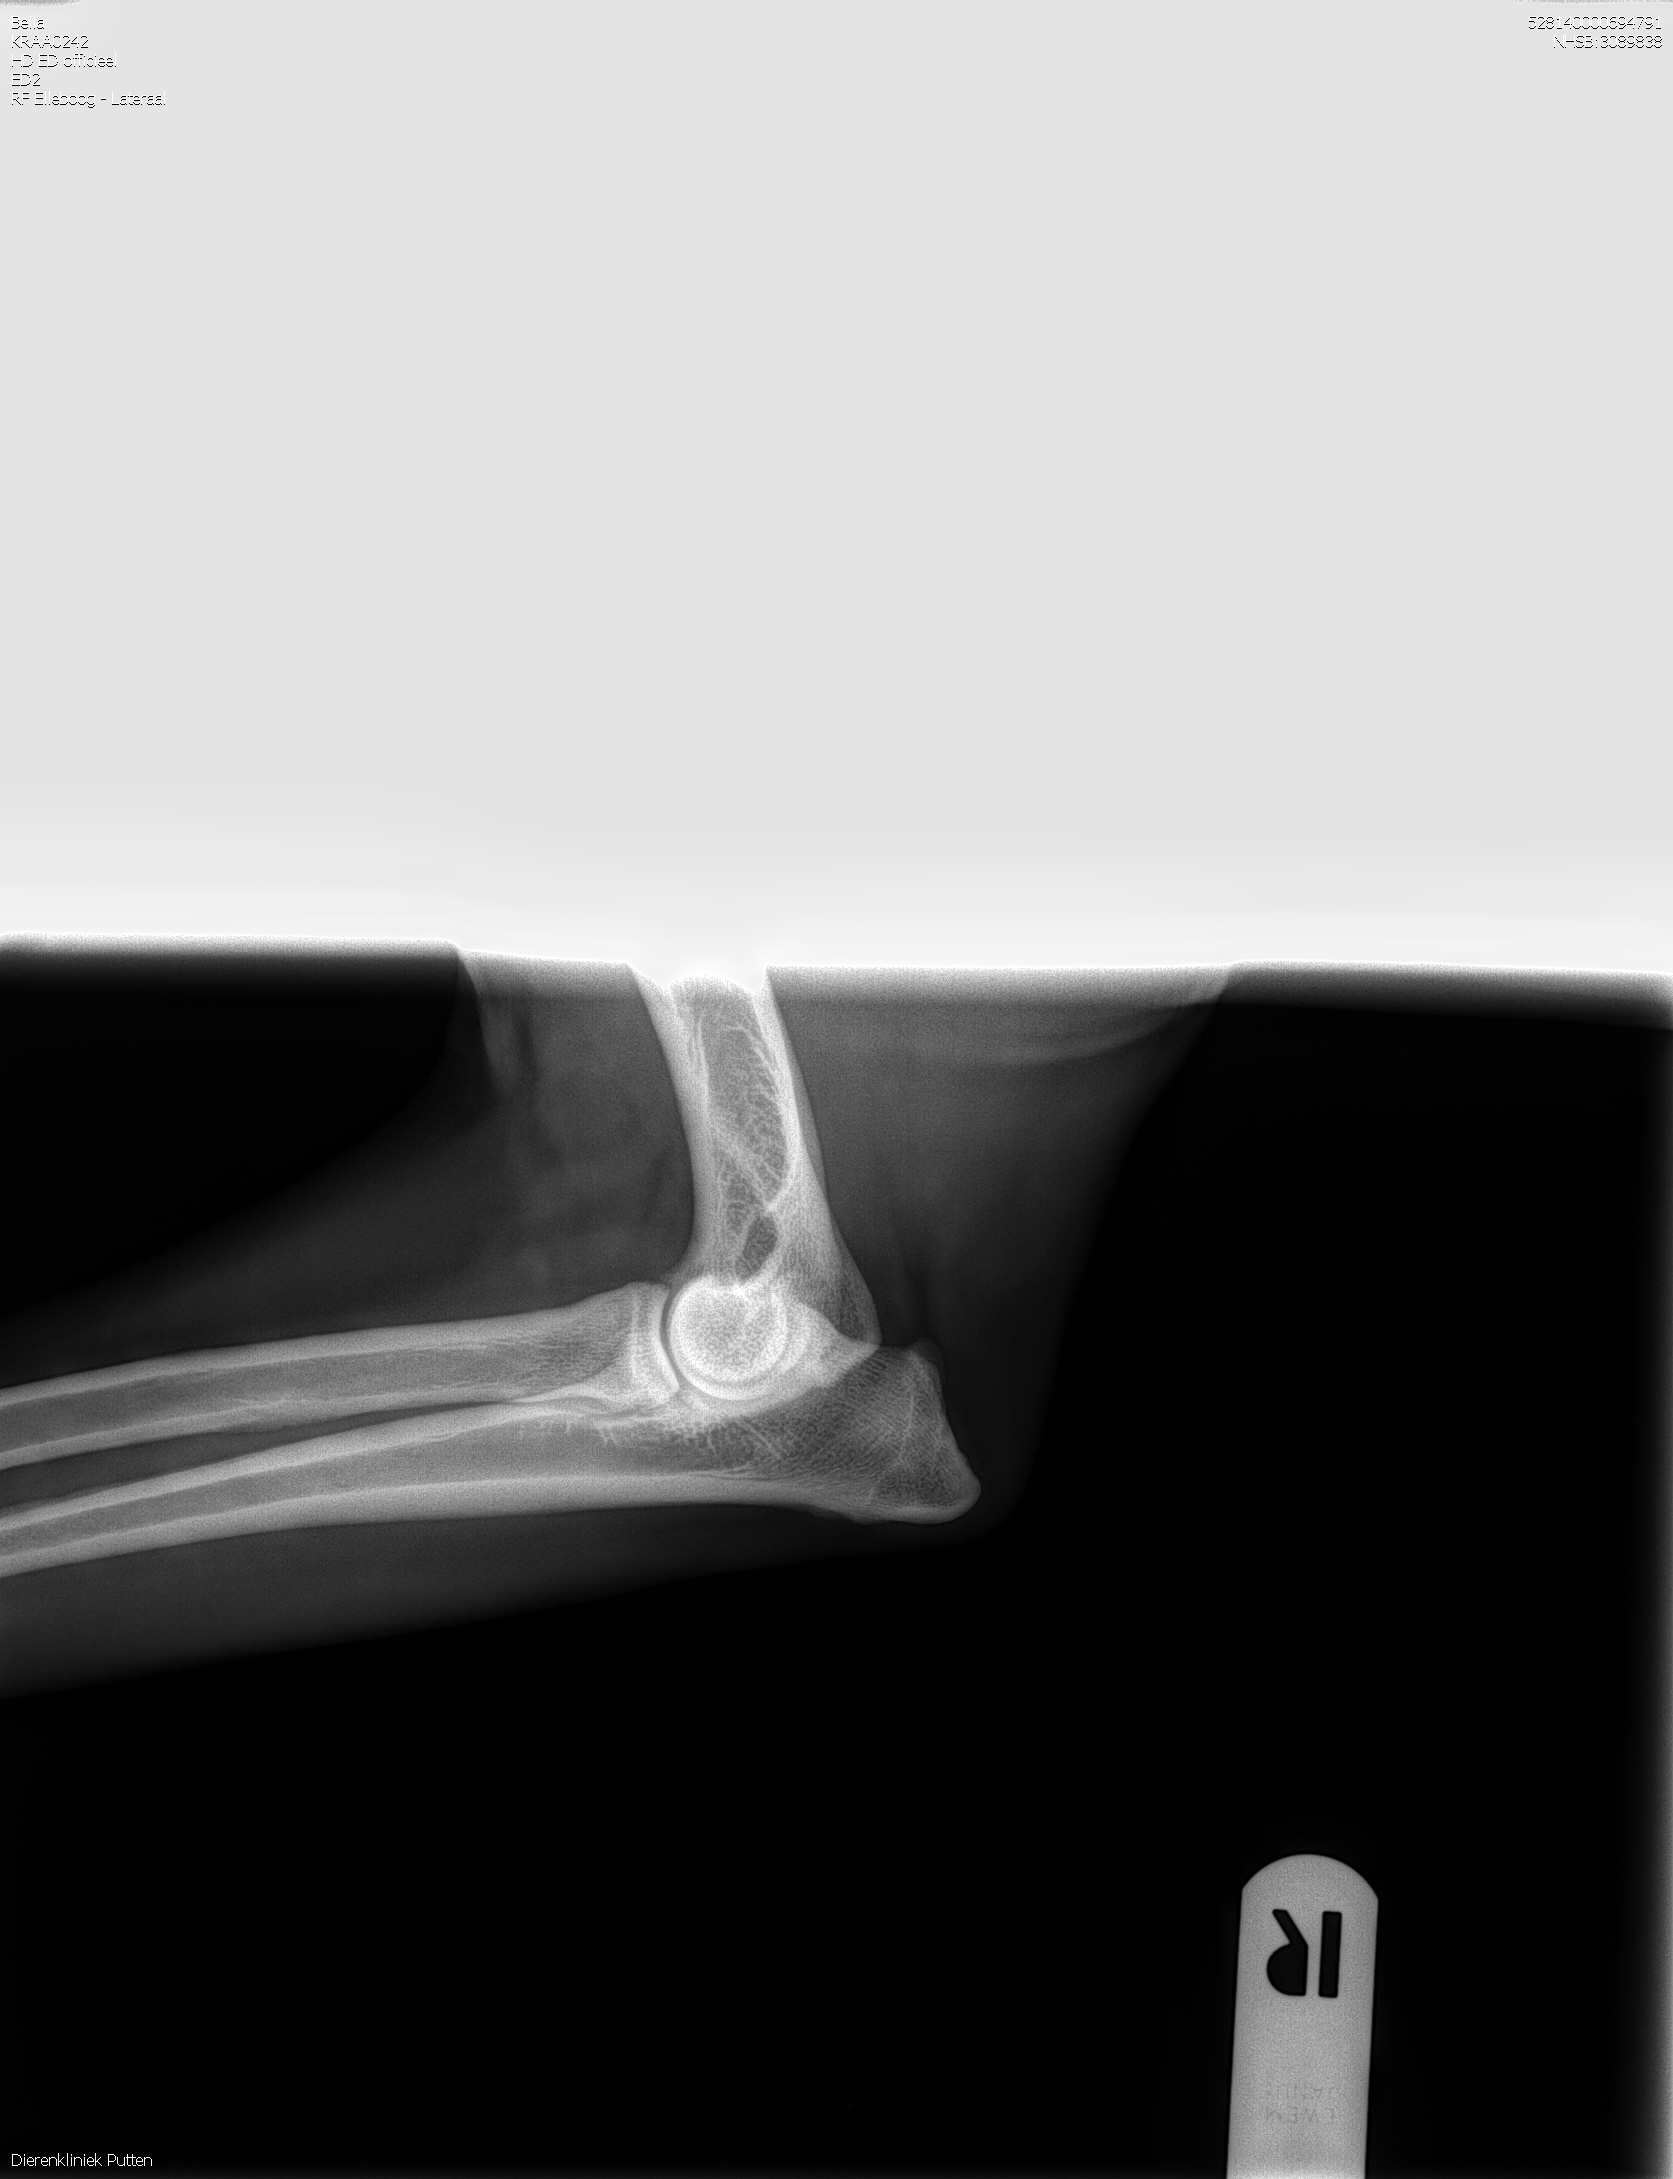

HD-A (Norbergwaarde 37.5, Botafw. 0), ED-0, Rug 100%

Röntgen foto’s Bella